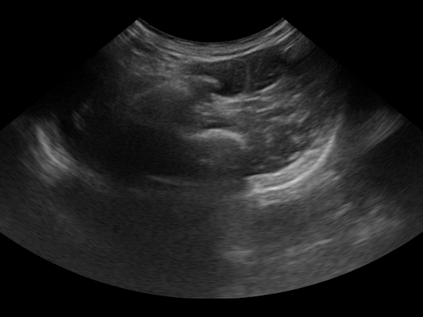

Three-dimensional (3D) freehand ultrasound (US) reconstruction without a tracker can be advantageous over its two-dimensional or tracked counterparts in many clinical applications. In this paper, we propose to estimate 3D spatial transformation between US frames from both past and future 2D images, using feed-forward and recurrent neural networks (RNNs). With the temporally available frames, a further multi-task learning algorithm is proposed to utilise a large number of auxiliary transformation-predicting tasks between them. Using more than 40,000 US frames acquired from 228 scans on 38 forearms of 19 volunteers in a volunteer study, the hold-out test performance is quantified by frame prediction accuracy, volume reconstruction overlap, accumulated tracking error and final drift, based on ground-truth from an optical tracker. The results show the importance of modelling the temporal-spatially correlated input frames as well as output transformations, with further improvement owing to additional past and/or future frames. The best performing model was associated with predicting transformation between moderately-spaced frames, with an interval of less than ten frames at 20 frames per second (fps). Little benefit was observed by adding frames more than one second away from the predicted transformation, with or without LSTM-based RNNs. Interestingly, with the proposed approach, explicit within-sequence loss that encourages consistency in composing transformations or minimises accumulated error may no longer be required. The implementation code and volunteer data will be made publicly available ensuring reproducibility and further research.